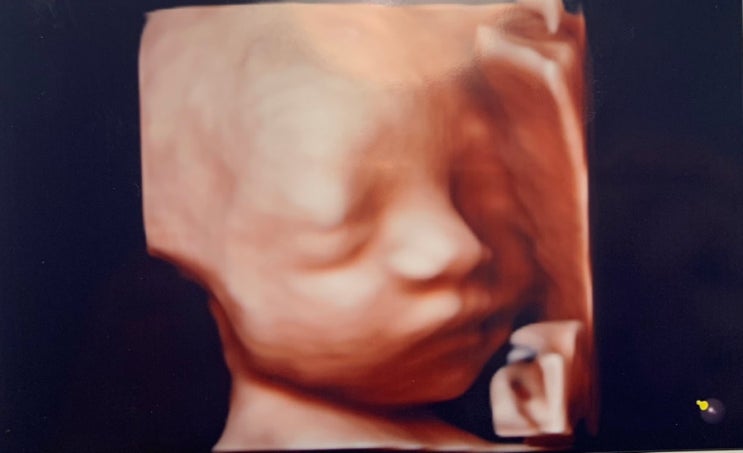

오늘 산부인과 정기검진이 있는 날이었습니다. 신랑도 반차를 내서 초음파도 같이 보고 백일해 예방접종도 ...